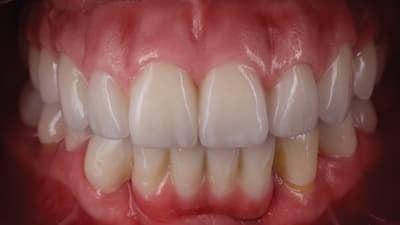

Step-by-Step Using Collaboration and Technology to Deliver By Victor Castro, CDT, Wesam Salha, DDS May 01, 2019 3 min read